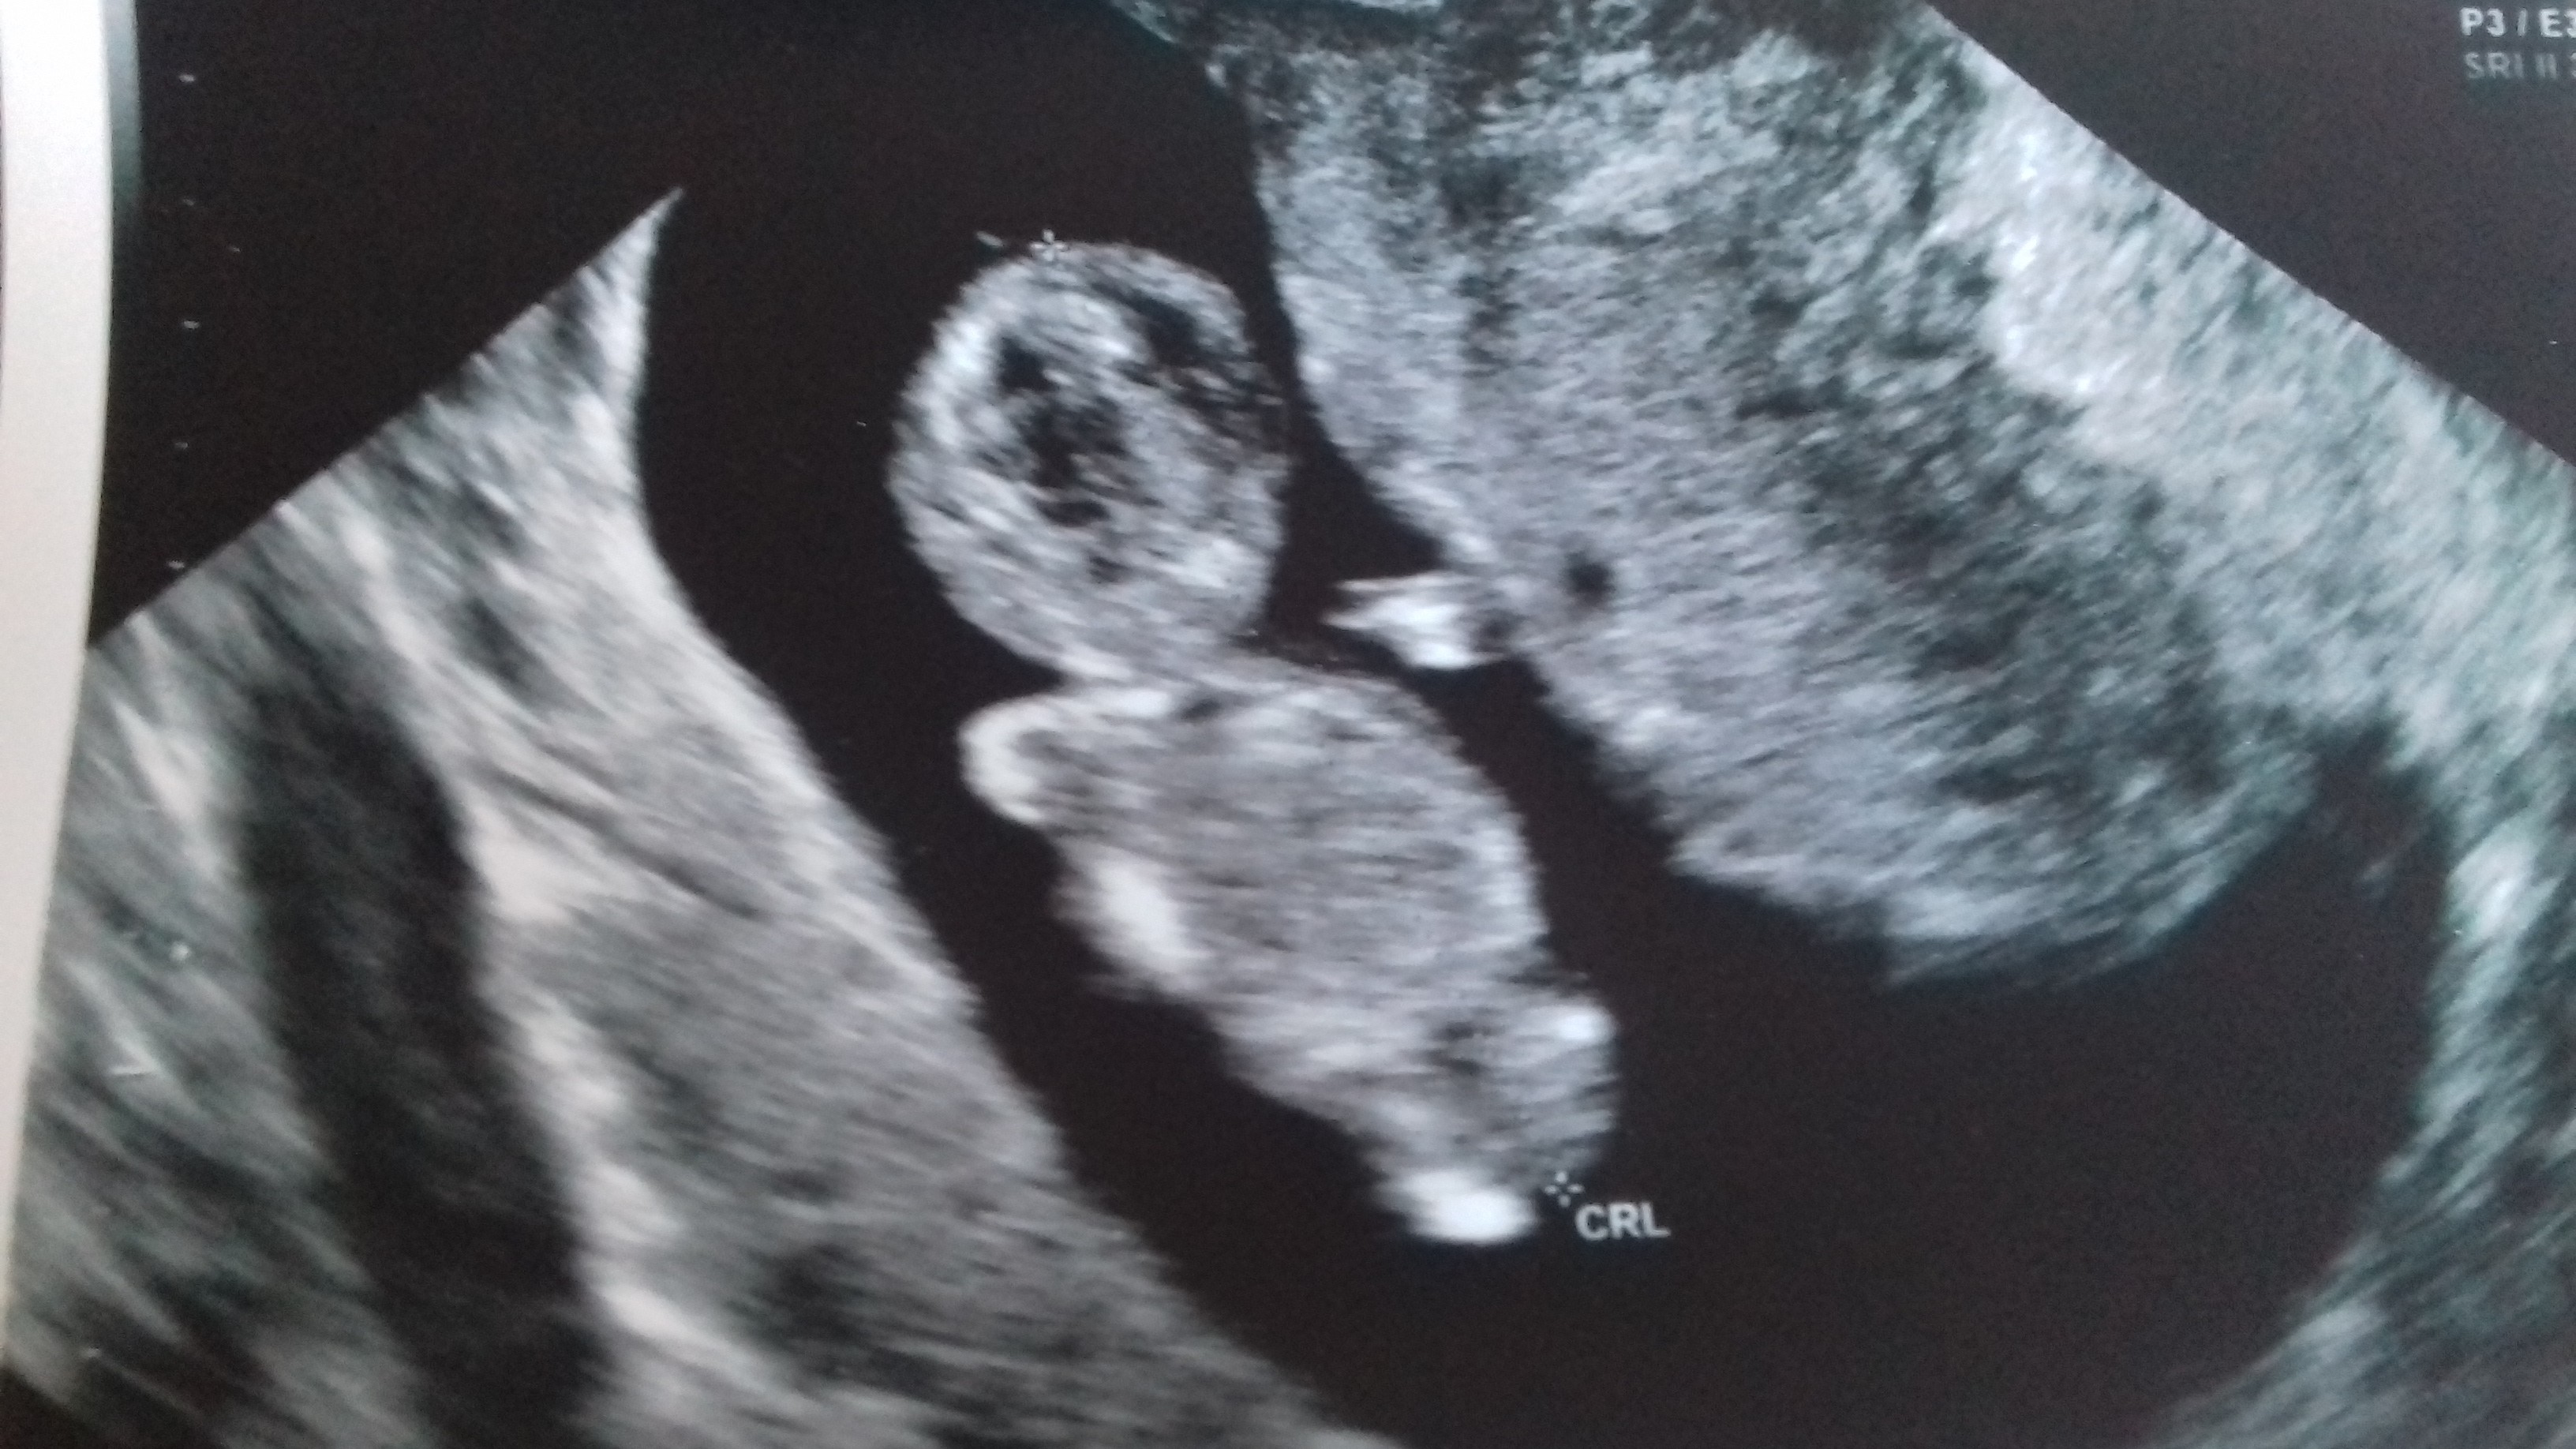

Dzidziulek ma już ponad 4 cm. Cały czas wychodzi równo "starszy" o tydzień wg usg w porównaniu z OM. Serduszko pięknie bije, nawet na chwilę lekarz mi dał posłuchać ale dosłownie na momencik żeby nie męczyć Bąbelka

ale jak to powiedział "na mój słuch bije idealnie". Dzidziuś sobie spał podczas usg ale potem się obudził i tak słodko przecieral rączkami buźke